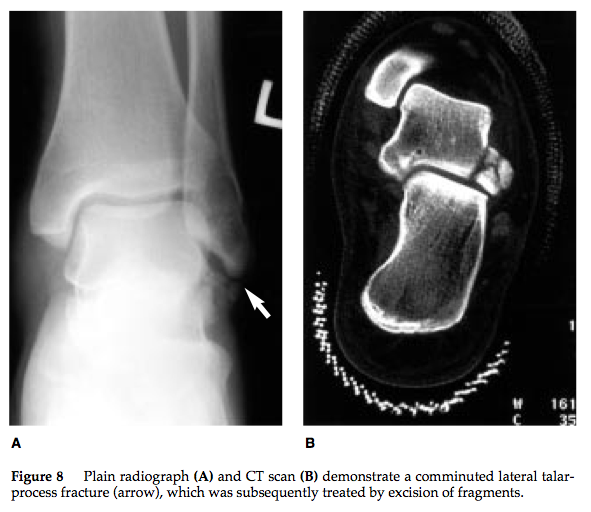

What is your approach to lateral process fractures

A

• Snowboarder’s fracture

• Mechanism

• dorsiflexion, axial loading, inversion, and external rotation

• often misdiagnosed as ankle sprain

• presents as ankle sprain that is not improving after 6 week

• Imaging

• Radiographs - may be falsely negative

• CT scan

• should be performed when suspicion is high (snowboarder) and radiographs are negative

• Treatment

• SLC for 6 weeks (NWB first 4 weeks)

• indicated if nondisplaced (< 2mm)

• ORIF/Kirshner wires via lateral approach

• indicated if displaced (> 2mm)

• Fragment excision

• indicated if comminuted

• incompetence of the lateral talocalcaneal ligament is expected with excision of a 1 cm fragment; no ankle or subtalar joint instability is created, however

How well did you know this?